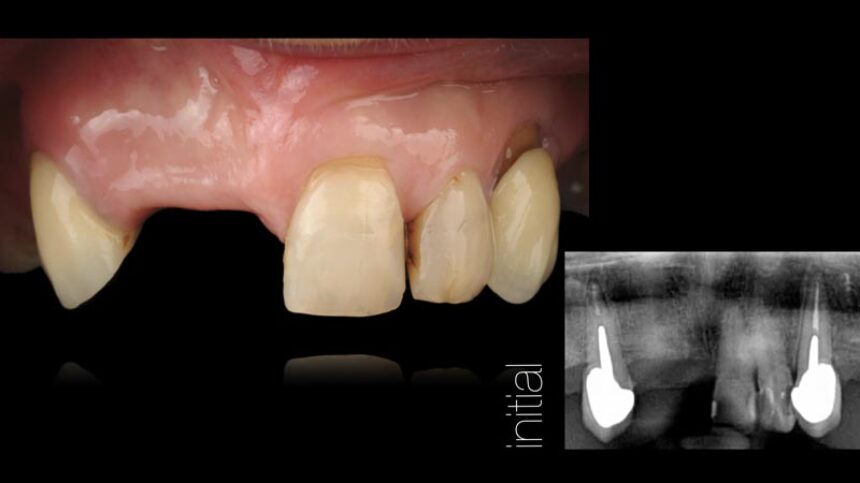

· Η έννοια του σχεδίου θεραπείας με άμεση τοποθέτηση, από την προσθετολογική στη χειρουργική επέμβαση

· βήματα της θεραπείας από την εξαγωγή του δοντιού ως την παράδοση της αποκατάστασης: οι λεπτομέρειες

· κριτήρια που σχετίζονται με τους μαλακούς ιστούς στη θεραπεία με άμεση τοποθέτηση εμφυτεύματος